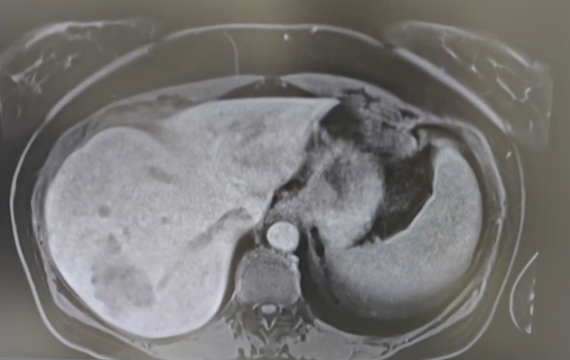

Beyond the 2D scan: A surgeon’s case for 3D liver reconstruction

For experienced liver surgeons, the ability to visualize complex anatomy is a deeply ingrained skill. Yet, relying on traditional 2D scans for preoperative planning in…